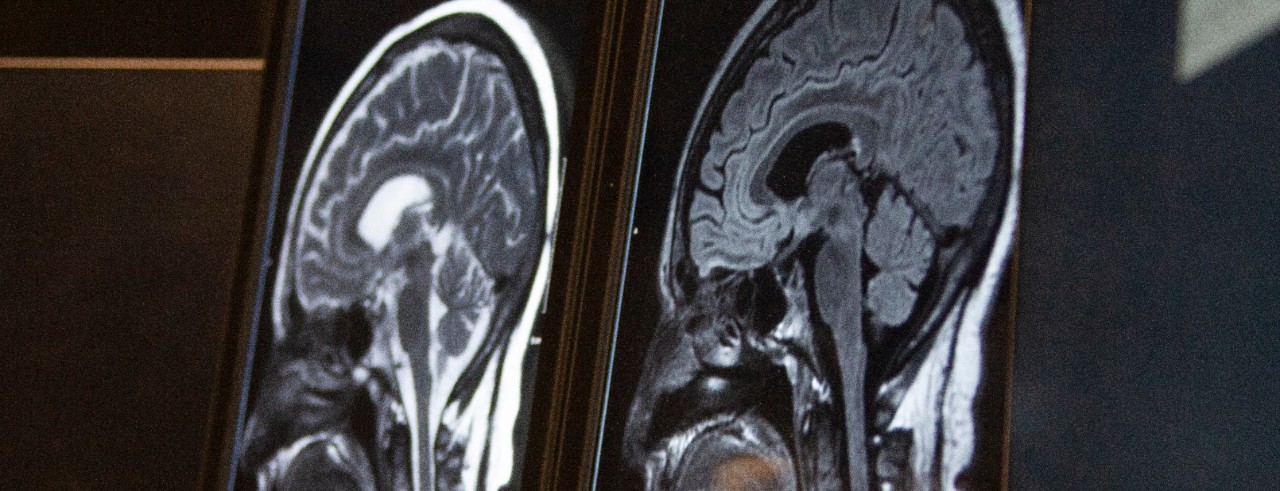

The University of Cincinnati’s Rhonna Shatz, DO, recently joined 55KRC’s Simply Medicine radio show and podcast following the announcement that actor Bruce Willis has been diagnosed with frontotemporal dementia.

Willis disclosed in 2022 that he had been diagnosed with aphasia, a language disorder that can look like problems with word choice or grammar. While not commenting directly on Willis’s case, Shatz said aphasia is often the first presenting symptom of a more specific neurological disorder.

“It’s not unusual for people in their 40s and 50s and 60s to have diseases like Alzheimer’s disease presenting with a language disorder, something we call primary progressive aphasia,” said Shatz, adjunct associate professor, division director for behavioral neurology, and the Bob and Sandy Heimann Endowed Chair in Research and Education in Alzheimer’s Disease in the UC College of Medicine and a UC Health physician.

Willis is 67 years old, and Shatz said symptoms of dementia can be different in younger populations compared to the “traditional” first symptom of memory loss.